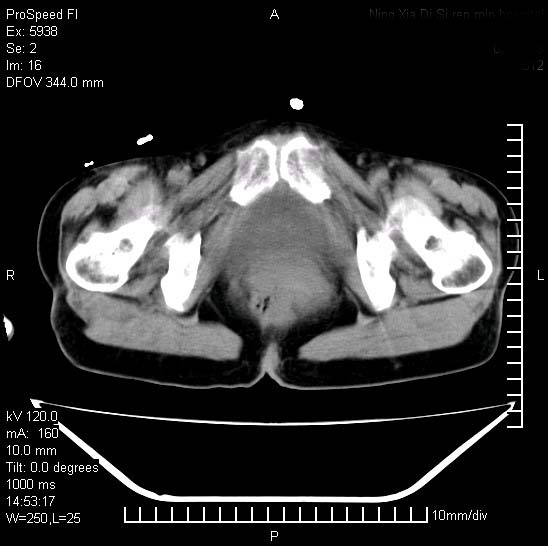

反复小腹疼痛,盆腔积液3年,无发热,曾抗痨一段时间。

结核性腹膜炎伴积液。右侧髂骨骨窗看看,是否有骨质破坏。

右下腹肠管壁增厚,边缘有侵润改变及点状低密度影,内侧可见局限性肿块。考虑-----淋巴瘤或增生型肠结核----盆腔积液-----建议肠镜检查